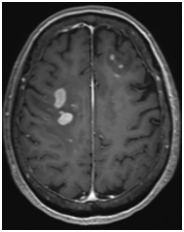

Background: Treatment for refractory or relapsed primary CNS lymphoma (r/r PCNSL) is challenging. Salvage whole-brain radiation therapy (WBRT) is an option but has a short duration of disease control, so additional treatment modalities are warranted. Case: A 75-year-old female with r/r PCNSL who had multiple progressions after multiple lines of treatment underwent salvage WBRT. The patient received ibrutinib, a Bruton's tyrosine kinase inhibitor, as maintenance therapy for 18 months following WBRT with the intention of increasing survival duration after salvage WBRT. She survived 81 months from diagnosis, including 57 months after completion of WBRT. Conclusion: This case presentation describes the experience of using ibrutinib as maintenance therapy in treating r/r PCNSL after salvage WBRT.

Abstract Image